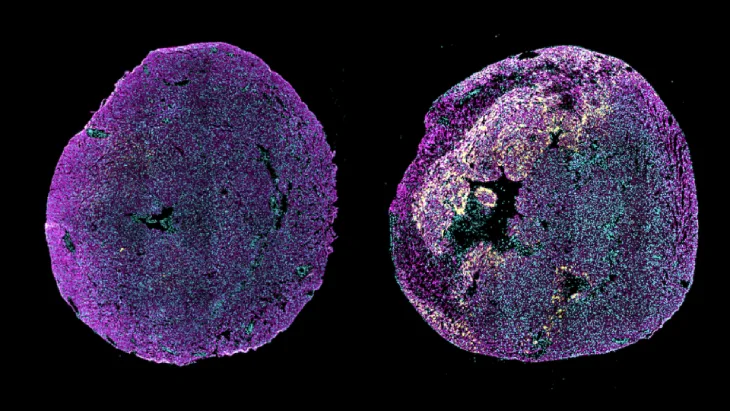

Moleküler düzeyde yapılan tek çekirdekli transkriptomik analizler, tedavinin kalpte prorejeneratif bir mikroçevre oluşturduğunu ortaya koydu. Buna göre natriüretik peptid reseptörü 1 pozitif endotel ve epikard hücrelerinin parakrin profili yeniden şekillendi, kardiyomiyositlerde hücre döngüsüne yeniden giriş desteklendi. Ayrıca periostin pozitif profibrotik fibroblastların genişlemesi baskılandı. Başka bir deyişle, tedavi yalnızca hasarı sınırlamakla kalmadı, bununla birlikte onarımı destekleyen biyolojik sinyalleri de güçlendirdi.